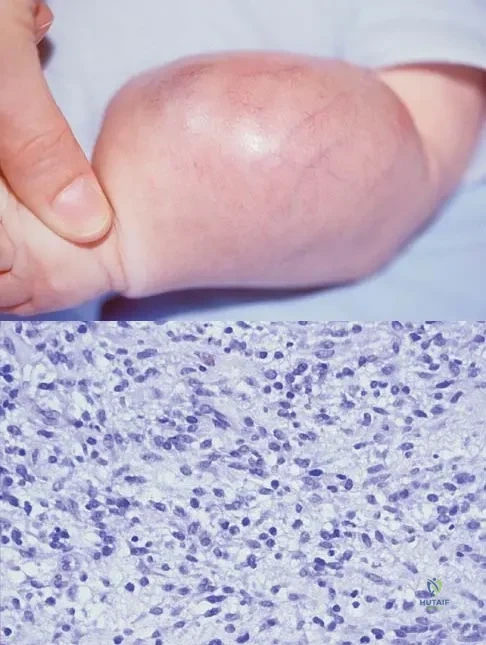

An infant is born with a mass that involves both the volar and dorsal compartments of the left arm. A clinical photograph and biopsy specimen are shown in Figures 41a and 41b. What is the best initial course of action?

Explanation